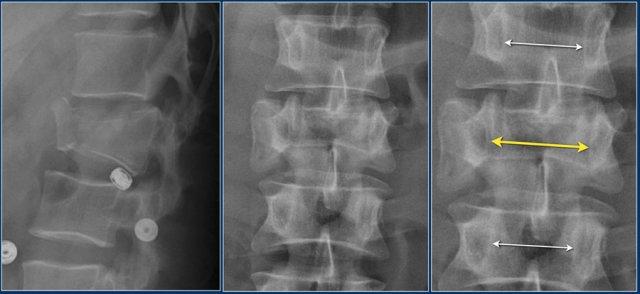

Giãn rộng khoảng cách liên cuống (interpedicular distance)

Giãn rộng khoảng cách liên cuống, thường là hệ quả của đường gãy theo mặt phẳng đứng dọc, gặp trong 80% các trường hợp gãy vỡ.

Hình chiếu bên cho thấy các đặc điểm điển hình của gãy vỡ.

Trên hình chiếu thẳng (AP), lưu ý sự giãn rộng kín đáo của khoảng cách liên cuống so với các tầng trên và dưới.

CT axial và MRI trên cùng một bệnh nhân cho thấy mảnh xương di lệch đang chèn ép vào bao màng cứng (thecal sac).

Trên CT và MRI mặt phẳng đứng dọc, không có dấu hiệu tổn thương dây chằng phía sau.

Dây chằng dọc trước bị đứt.

Khớp mặt bên phải trông hơi giãn rộng trên CT và có dịch trong khớp trên MRI.

Nếu có nhiều dịch trong khớp, chúng ta nên xếp loại là không xác định.

Trong trường hợp này, chúng ta chưa chắc chắn.